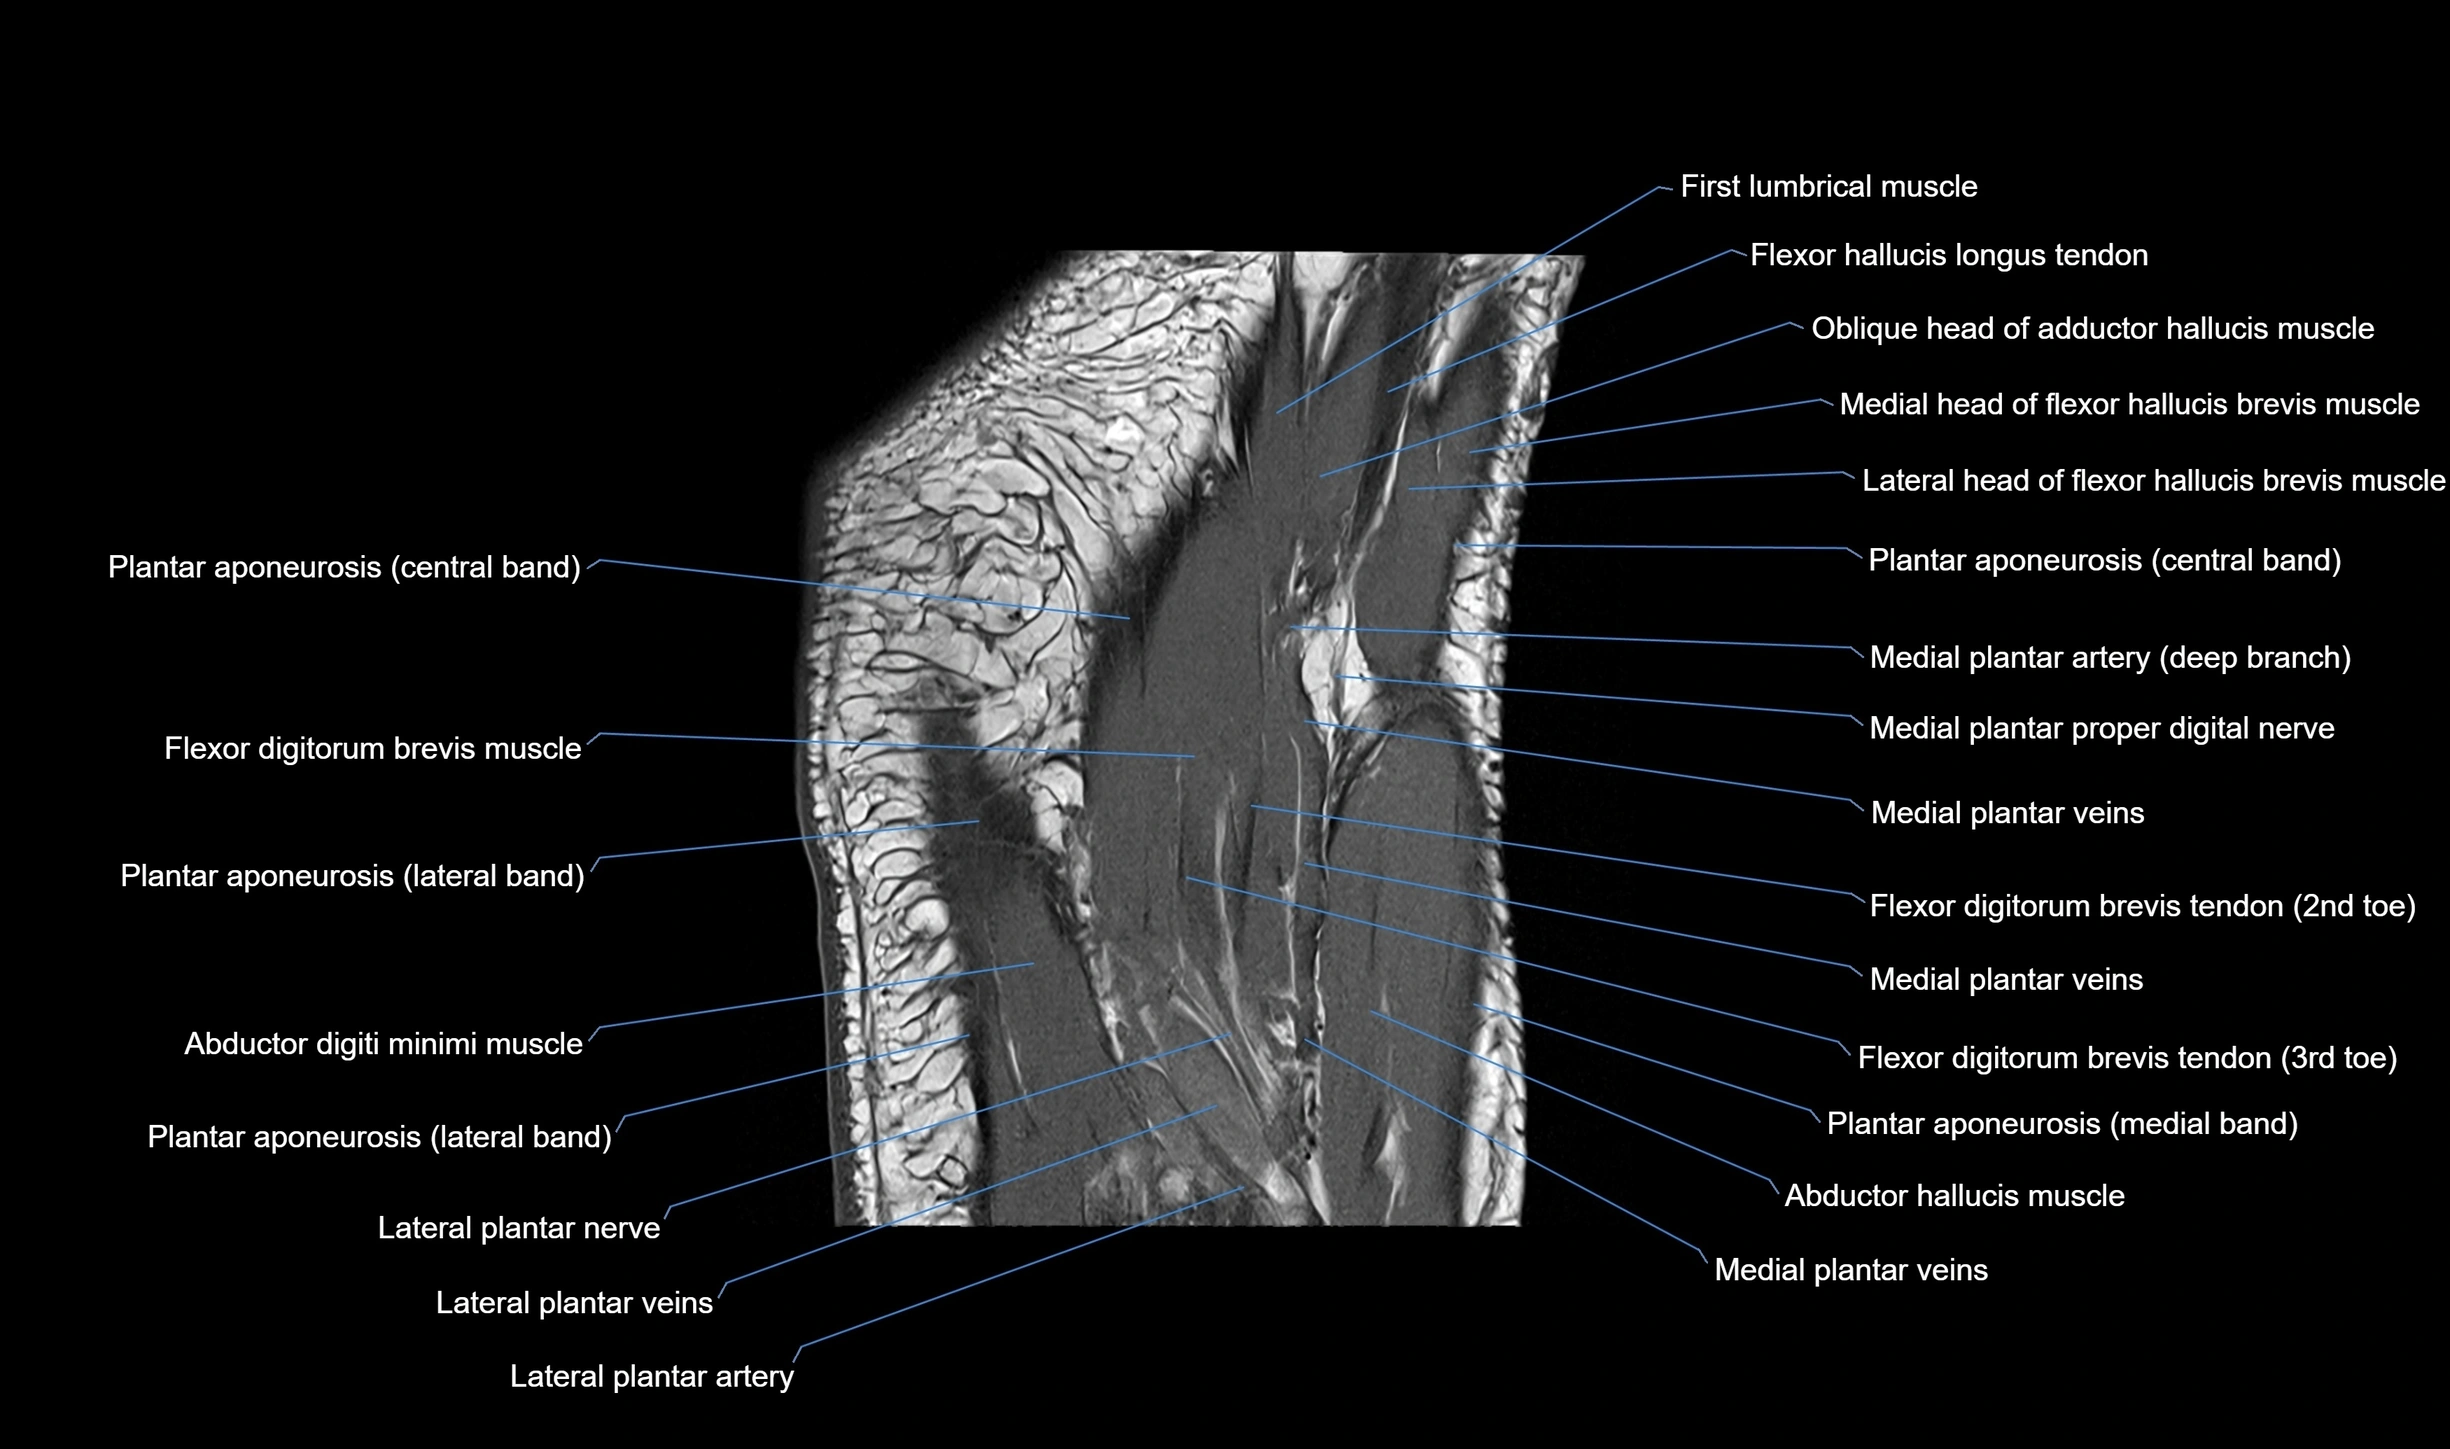

MRI image